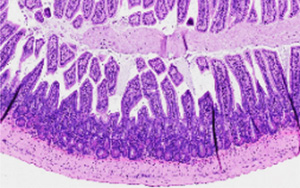

一種化合物可以逆轉小鼠的腸道炎癥

索爾克研究所的研究人員開發(fā)的藥物就像腸道中的主復位開關。這種化合物被稱為FexD,此前已被發(fā)現(xiàn)可以降低膽固醇、燃燒脂肪,并預防小鼠的結直腸癌。現(xiàn)在,2022年12月12日《PNAS》報道,F(xiàn)exD還可以預防和逆轉炎癥性腸病小鼠模型的腸道炎癥。